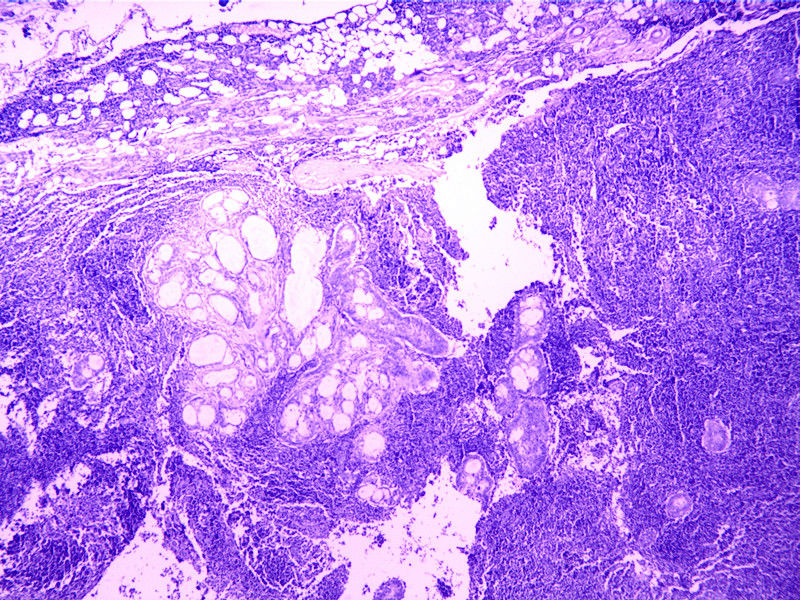

• 性别 年龄 46 临床诊断 肿物

临床症状 发现肿物3年

标本名称 腮腺

大体所见 肿物V3*2.5*2.5cm,界清。

肿瘤应该没问题,但不一定是粘表,因为片子里有成巢的胞浆透亮细胞,但该细胞并不像黏液上皮,更像是皮脂细胞,并与涎腺导管相混合,背景为弥漫的淋巴细胞,考虑为皮脂淋巴腺瘤。良性,彻底切除可治愈。需要与淋巴上皮癌鉴别。

形态符合皮脂腺淋巴腺瘤/癌,目前没有明显癌的证据,至于淋巴细胞也需要了解是否为肿瘤性增生

以淋巴组织为背景的涎腺病变一般有:淋巴上皮囊肿;warthin瘤;皮脂和非皮脂淋巴腺瘤。本例出现了皮脂样透明细胞及与涎腺导管混合存在,背景为弥漫淋巴细胞,且肉眼界清,在下拙见:更倾向是皮脂淋巴腺瘤。大家热烈讨论啊!